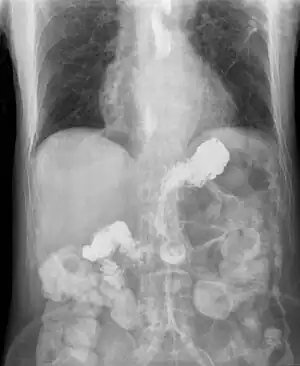

Radiografia em que se observa o contraste a voltar a entrar no esófago devido a refluxo grave

Os fatores de risco incluem obesidade, gravidez, fumar, hérnia do hiato e alguns medicamentos.[1] Os medicamentos envolvidos mais comuns são anti-histamínicos, bloqueadores dos canais de cálcio, antidepressivos e indutores do sono.[1] A doença é causada por uma disfunção do esfíncter esofágico inferior, a união entre o estômago e o esófago, que não encerra por completo.[1] Em pessoas que não melhoram com medidas de tratamento simples, podem ser necessários métodos complementares de diagnóstico, como endoscopia digestiva alta, radiografias com contraste, phmetria esofágica ou manometria esofágica.[1]